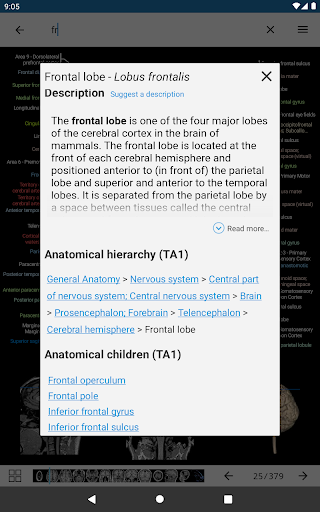

* تحسين رؤية تعريفات الأجزاء التشريحية

* تصفح بين الأجزاء التشريحية باستخدام روابط الوصف

- يتم الآن عرض المصطلحات المتعلقة بالهيكل التشريحي في عرض التفاصيل - تمت إضافة